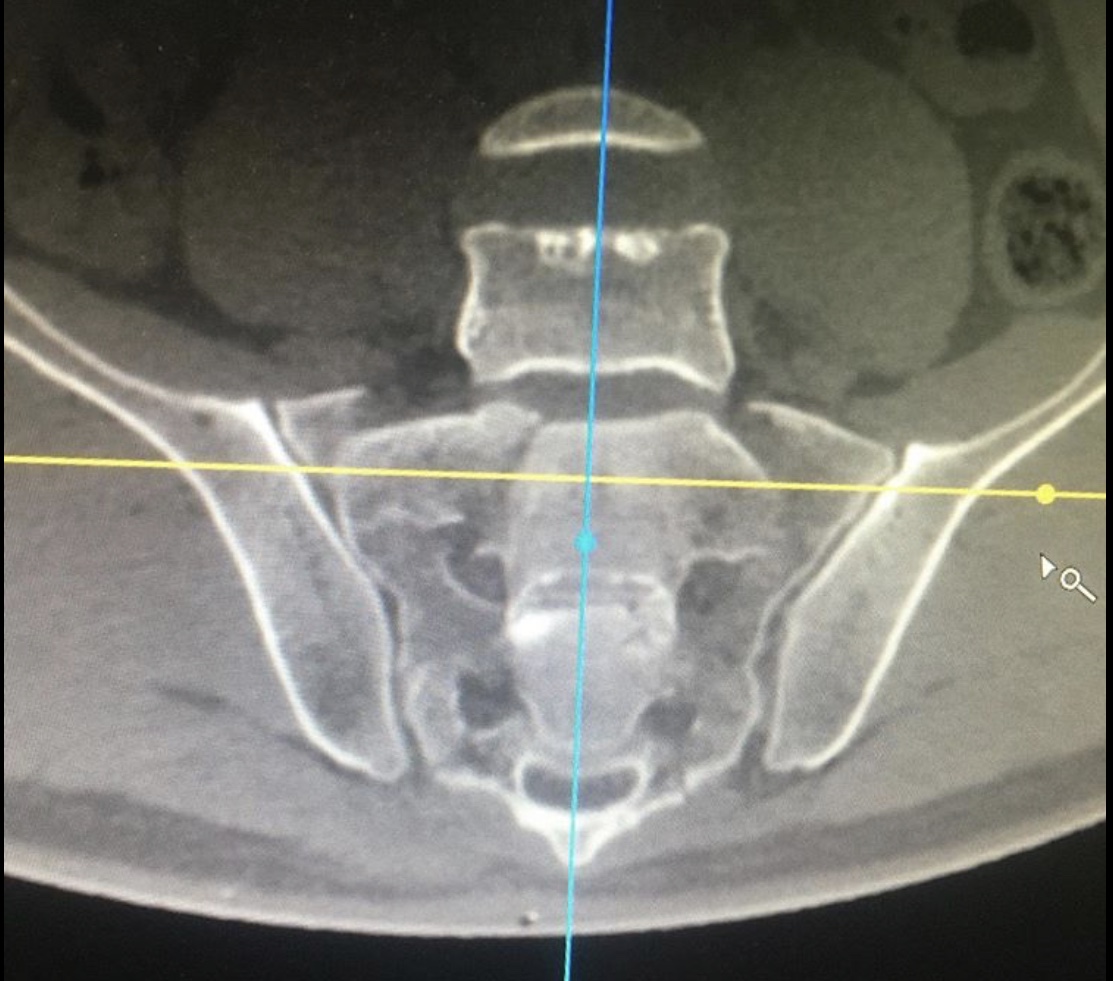

Диагноз неутешительный: двусторонний нестабильный перелом крестца, осложнённый каудопатией и нарушением функции тазовых органов, перелом типа RoyCamille 2 с компрессией корешков конского хвоста.

Как рассказал хирург – травматолог – ортопед нашей клиники Руслан Ильгизарович Закиров, при поступлении пациенту была выполнена стабилизация костей таза в аппарате внешней фиксации. После стабилизации гемодинамических показателей выполнена двусторонняя пояснично-тазовая фиксация, сакротомия на вершине деформации, остеосинтез реконструктивными пластинами.